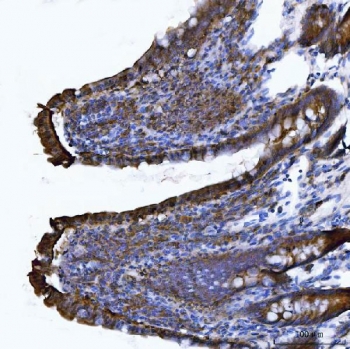

IHC staining of FFPE rat colon tissue with Itgae antibody. HIER: boil tissue sections in pH8 EDTA for 20 min and allow to cool before testing.

IHC staining of FFPE mouse colon tissue with Itgae antibody. HIER: boil tissue sections in pH8 EDTA for 20 min and allow to cool before testing.